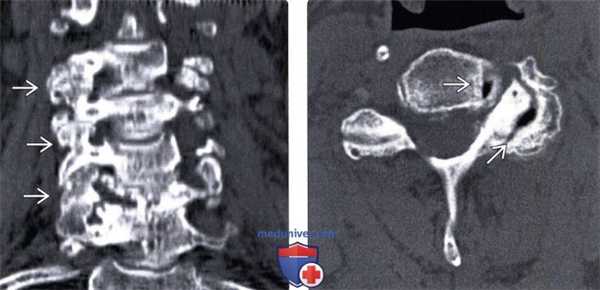

(Слева) На корональной КТ без КУ определяется тяжелая многоуровневая гипертрофическая дегенеративная артропатия дугоотростчатых суставов со стенозом межпозвонковых отверстий.

(Справа) На аксиальной КТ без КУ определяется тяжелая левосторонняя дегенеративная артропатия дугоотростчатого сустава со стенозом межпозвонкового отверстия. Определяется вакуум - феномен дугоотростчатого сустава и унковертебрального сустава.

(Слева) КТ, фронтальный срез: признаки выраженной многоуровневой дегенеративной гипертрофической артропатии дугоотростчатых суставов с фораминальным стенозом.

(Справа) КТ, аксиальный срез: признаки выраженного дегенеративного поражения левого дугоотростчатого сустава и фораминального стеноза. В полости дугоотростчатого и унковертебрального сустава отмечается «феномен вакуума».